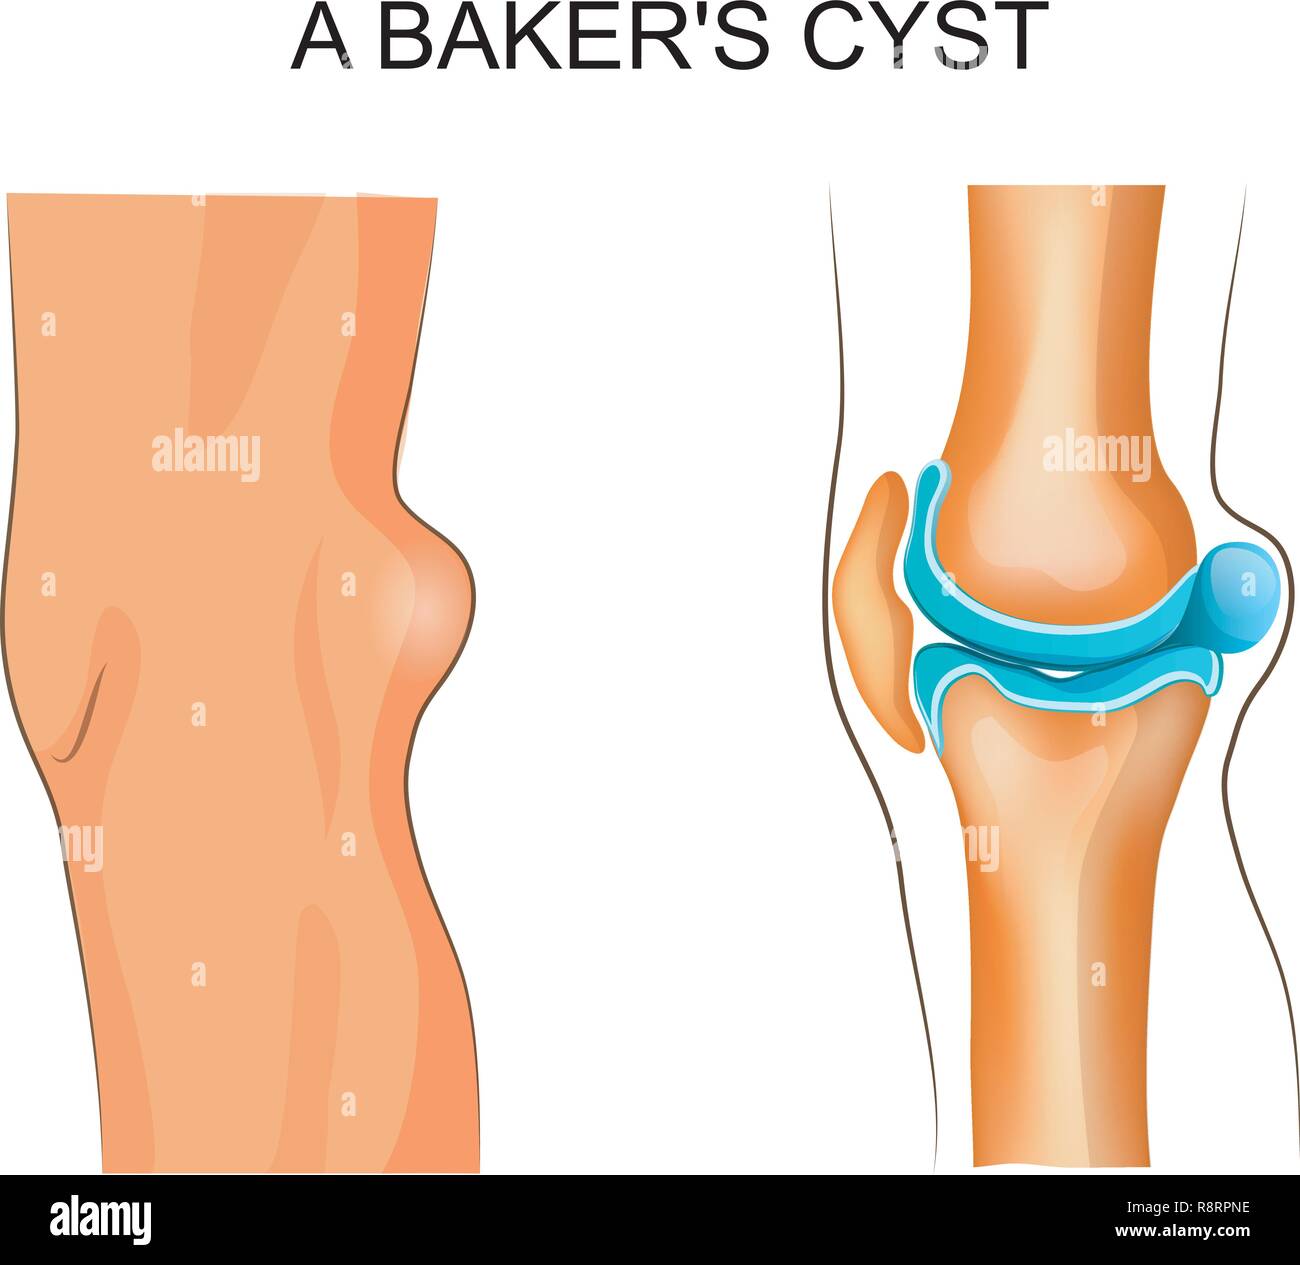

vector illustration of Baker's cyst. traumatology and orthopedics Stock Vectorhttps://www.alamy.com/image-license-details/?v=1https://www.alamy.com/vector-illustration-of-bakers-cyst-traumatology-and-orthopedics-image229174778.html

vector illustration of Baker's cyst. traumatology and orthopedics Stock Vectorhttps://www.alamy.com/image-license-details/?v=1https://www.alamy.com/vector-illustration-of-bakers-cyst-traumatology-and-orthopedics-image229174778.htmlRFR8RPNE–vector illustration of Baker's cyst. traumatology and orthopedics